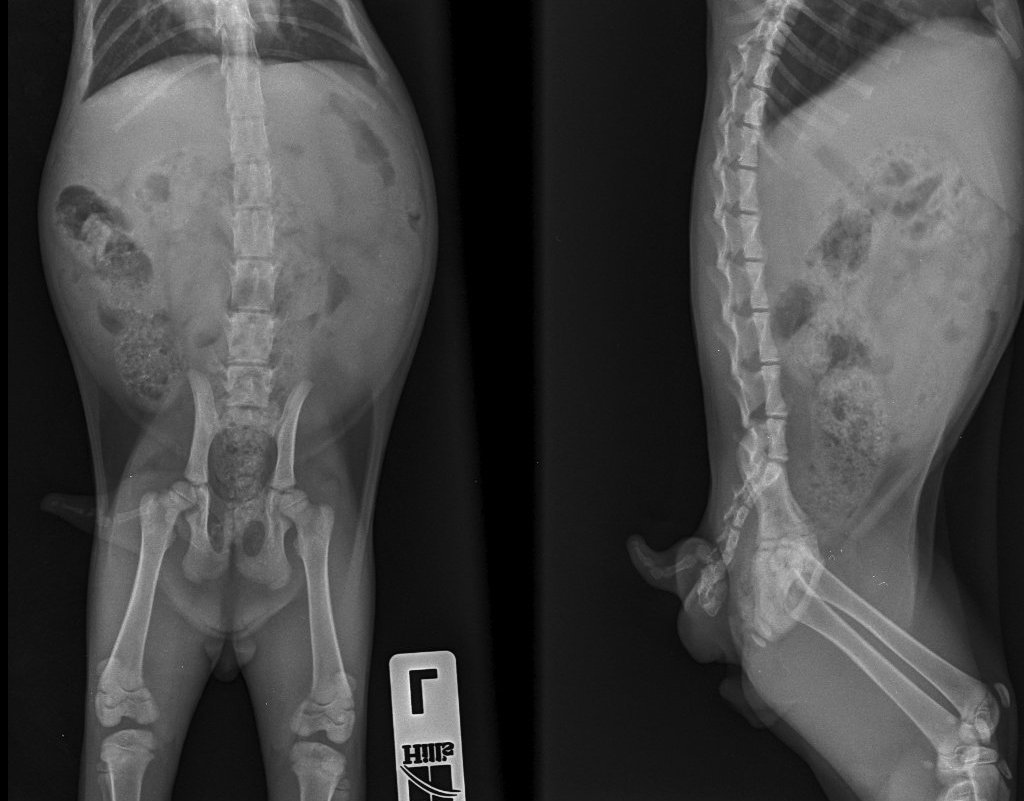

Лікувальні заходи, спрямовані на нездатність утримувати сечовипускання, призначає тільки ветеринар після детального обстеження та складання анамнезу. Діагностика проводиться кількома комбінованими методами: візуальним оглядом, пальпацією, збором аналізу сечі, проведенням додаткових ультразвукових досліджень або рентгеном.

Рентген, нетримання калу і сечі у кота